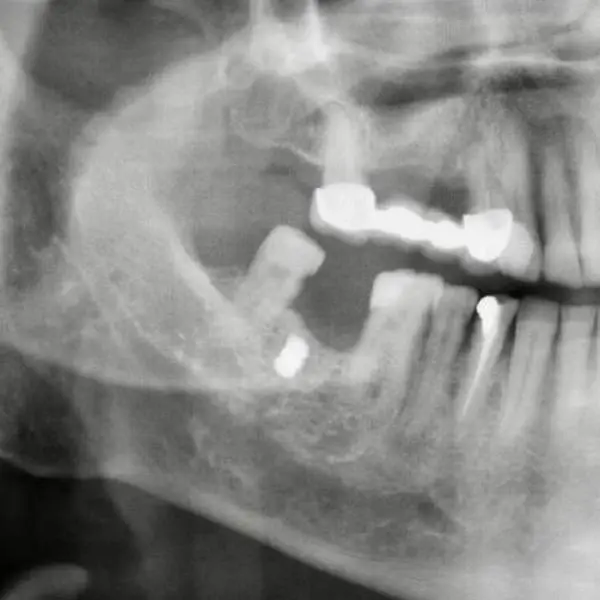

Erzincan'ın merkeze bağlı Aslahlı Mahallesi'nde evli ve 2 çocuk babası emekli memur Faik Akın, Binali Yıldırım Üniversitesi Ağız ve Diş Sağlığı Eğitim ve Araştırma Hastanesi Ağız Diş ve Çene Cerrahisi Bölümü'ne diş tedavisine gitti. Akın'ı muayene ettikten sonra çekilen röntgen filmini inceleyen Dr. Öğretim Üyesi Yakup Gülnahar, yanağında bir parça olduğunu belirledi.

Muayenede 15 yıl önce yaşadığı bir olayı hatırlayan Akın, benzinli hızar ile odun kestiği sırada zincirin koptuğunu ve daha sonra yanağında şişlik oluştuğunu söyledi. Dr. Gülnahar'ın mıknatıs ile yaptığı kontrolde parçanın metal olduğu tespit edildi. Dr. Gülnahar, ameliyat ile Akın'ın yanağındaki metal zincir parçasını aldı.

Diş tedavisine gelince metal parçanın röntgen ile görüldüğünü belirten Faik Akın Dr. Öğretim Üyesi Yakup Gülnahar, ağzımdaki şişliğin implant parçası olup, olmadığını sordu. Ben de kendisine implant yaptırmadığımı söyledim. Sonra aklıma 15 yıl önce yaşadığım hızar kazası geldi ve doktora anlattım. Yakup bey, mıknatıs ile kontrolü sonrası yanağımdaki parçanın metal olduğunu belirledi. 15 yıl önce benzinli hızar ile çalışırken zincir koparak çeneme çarpmıştı. Parça yanağıma girmiş ve bunu fark etmemişim. 15 yıl yanağımdaki bu şişlikle yaşadım. Başarılı bir operasyon ile aldılar. Şu anda hiçbir şeyim yok dedi.

Dr. Öğretim Üyesi Yakup Gülnahar da Faik bey, rutin diş tedavisi için bize geldi. İstenilen röntgen filminde bir cisme denk geldik. Kendisine 'İmplant yaptırdınız mı' diye sordum. 'Hayır' dedi. Bu sefer, hasta geçmişinde yaşadığı bir kazadan bahsetti. Kontrol ettiğimiz de mıknatısın şişliği çektiğini gördük. Başarılı bir operasyon ile demir parçasını aldık. Hasta şu anda gayet iyi diye konuştu.